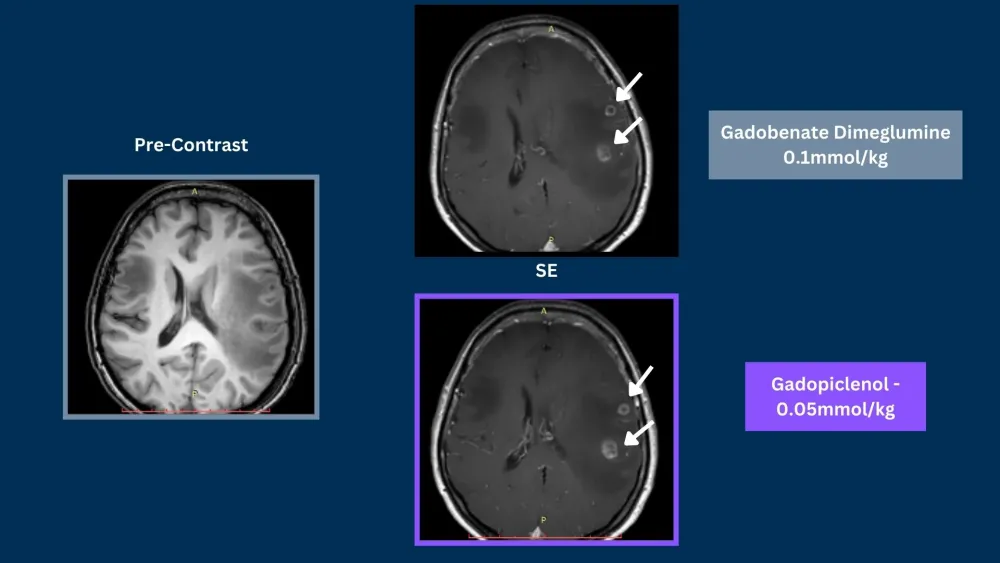

Phase III clinical trials, in CNS and Body, demonstrated that gadopiclenol at a dose of 0.05 mmol/kg was noninferior to gadobutrol at a dose of 0.1 mmol/kg in terms of lesion visualization.5,6

SE = Spin Echo, GRE = Gradient Echo, 3DGRE = 3D Gradient Echo, TSE = Turbo Spin Echo

Phase III PROMISE trial in the body demonstrated that gadopiclenol at a dose of 0.05 mmol/kg was noninferior to gadobutrol at a dose of 0.1 mmol/kg in terms of lesion visualization.6

Phase III PICTURE trial in CNS demonstrated that gadopiclenol at a dose of 0.05 mmol/kg was noninferior to gadobutrol at a dose of 0.1 mmol/kg in terms of lesion visualization.5